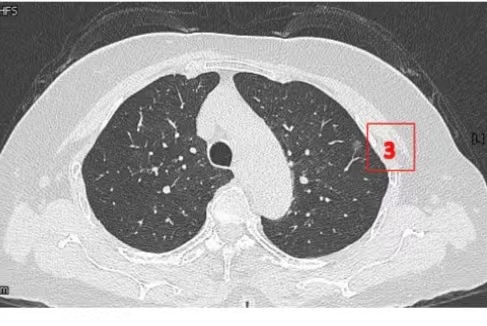

患者女性,71岁,因“发现左肺多发结节2周”入院。胸部CT提示左肺多发磨玻璃结节,较大者位于左肺上叶,呈类圆形,边界清晰,最大直径约9mm。该CT表现高度提示恶性可能。鉴于患者结节数量较多,为减少术中肺组织损伤,术前于CT引导下行经皮肺结节定位术,继而实施胸腔镜下左肺楔形切除术。术中共切除肺部结节6枚。术后病理示:左肺上叶较大结节(4号)为微浸润腺癌,其余5枚结节均为原位癌。患者术后恢复良好,于术后第1天拔除胸腔引流管,第4天顺利出院。

▲术前定位